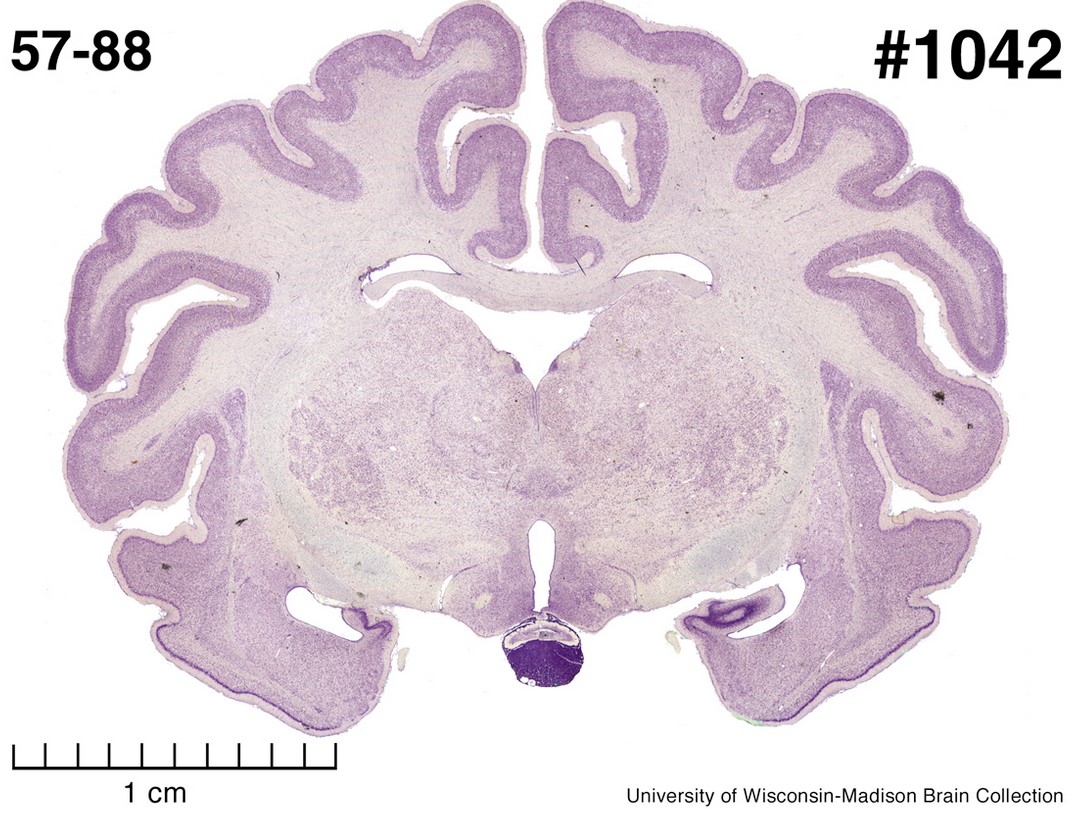

We will cover a variety of foundational and contemporary issues in human neuroscience, and will engage in discussion of scientific methods and techniques used to investigate the relationship between the function of brain systems, behavior, and cognition. The course will primarily emphasize functional neuroanatomy, higher cognitive and emotional function (cognitive and affective neuroscience), the neurobehavioral underpinnings of pathology in humans (clinical neuroscience), and an emerging field known as “positive” neuroscience. Laboratory sections allow students to engage with neuropsychological, cognitive, and psychophysiological research techniques. Both the lecture and laboratory heavily stress experimental design, data analysis, and scientific reasoning/information literacy. However, we also get to play with brains. Brains are rad.